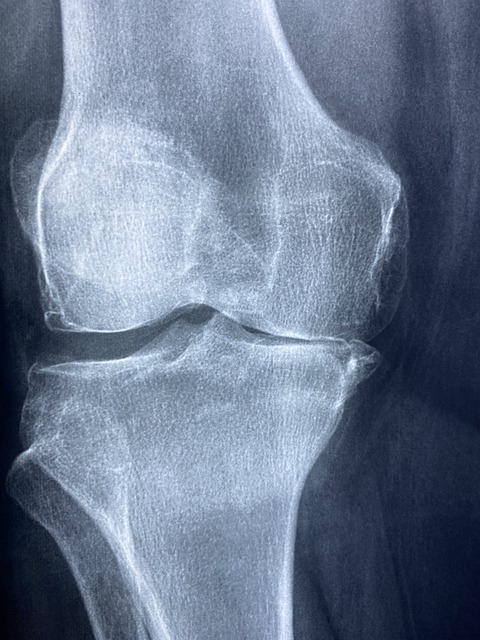

4.3 영상 검사

- X-ray

- 관절 공간의 축소, 연골 손상 확인.